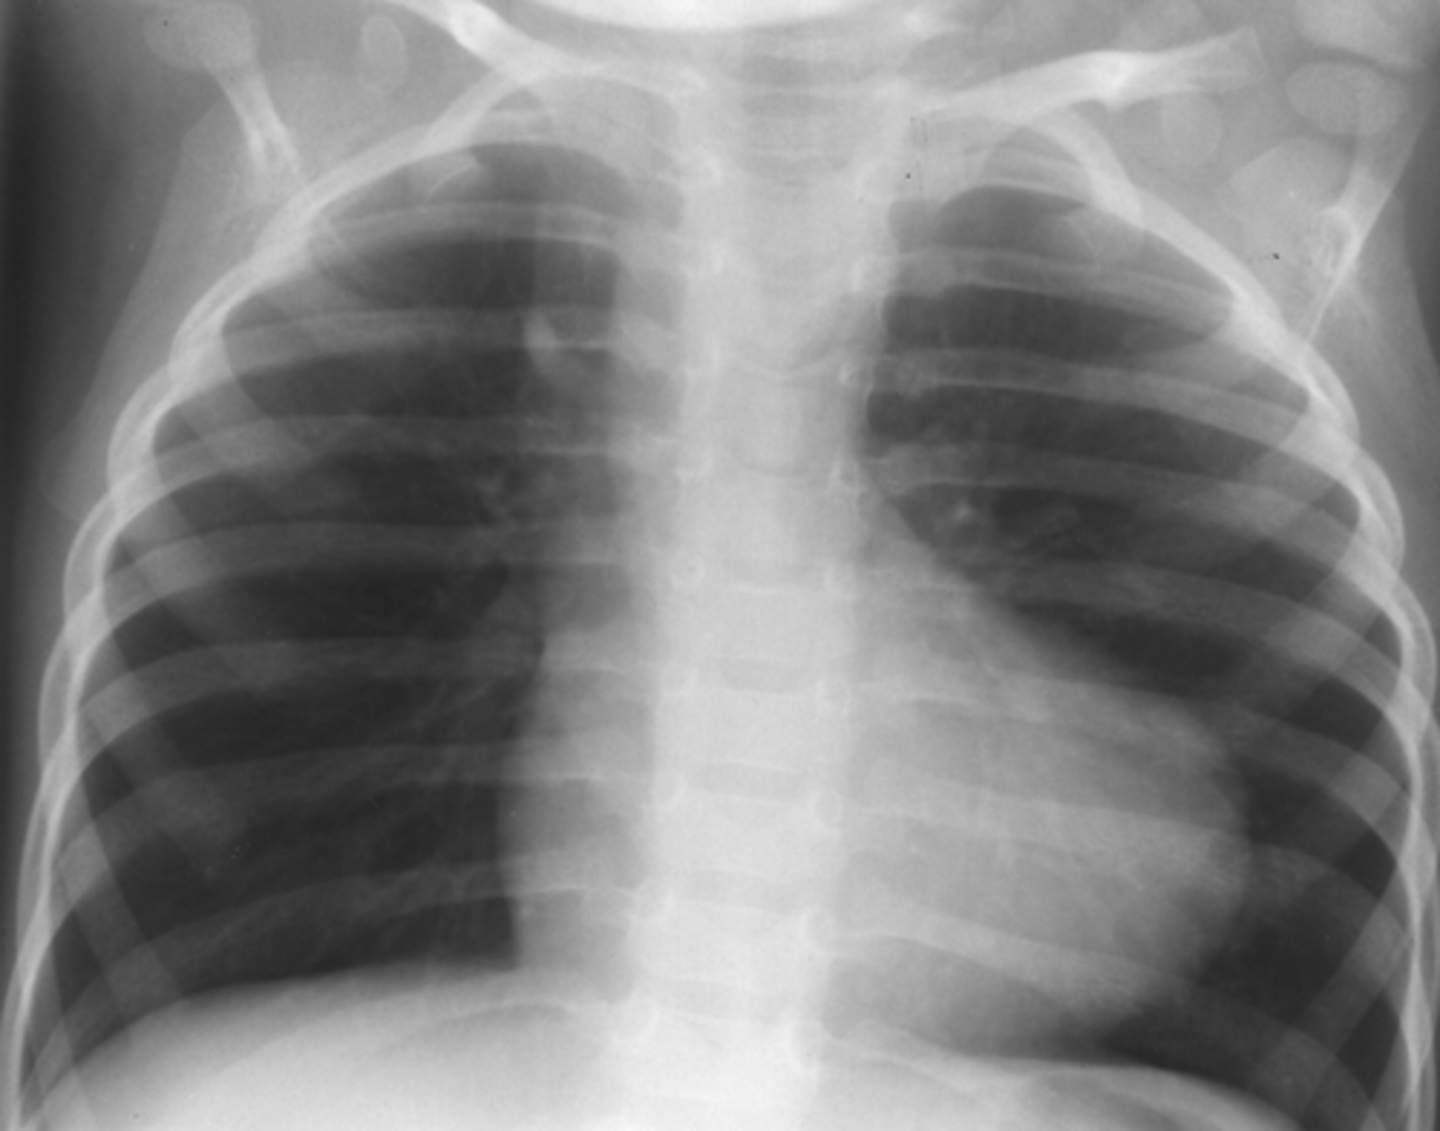

tetralogy of fallot is what type of shunt?

What are the defects

1.

2.

3.

4.

right to left

1. VSD

2. R ventricular hypertrophy

3. overriding aorta

4. pulmonic stenosis (RV outflow obstruction)

(photo: boot-shaped heart)